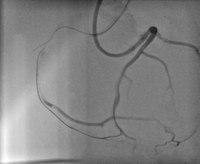

◆ 「3Dプリンタを用いたX線透視対応心臓カテーテルシミュレーターの発明」 ――― HEARTROID PROJECTが全国発明表彰「未来創造発明奨励賞」を受賞 「令和3年度全国発明表彰」(公益社団法人発明協会主催)において、大阪大学大学院医学系研究科循環器内科学講座の坂田泰史教授、大阪大学国際医工情報センターの岡山慶太特任講師(常勤)らの「3Dプリンタを用いたX線透視対応心臓カテーテルシミュレーターの発明」が「未来創造発明奨励賞」を受賞しました。未来創造発明奨励賞は中小・ベンチャー企業並びに大学及び公的研究機関に係わる発明が対象で、特に優秀と認められる発明に贈られます。 また、この受賞と合わせて、大阪大学が「未来創造発明貢献賞」を受賞しました。なお、今回の受賞で大阪大学は3年連続での受賞となります。 ⇒詳細はこちら

写真左:本発明による心臓カテーテルシミュレーター 写真右:心臓カテーテルシミュレーターを用いたX線透視下での手術画像